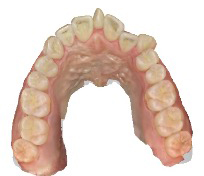

患者さんの年齢 20代 女性 症状 自分の歯が嫌い 治療内容 セラミック治療 費用 費用200万(税抜) 治療期間・回数 治療期間1ヶ月・通院回数3回 メリット 治療期間・回数が少ない デメリット・リスク 術後知覚過敏が起こる事ある - セラミック治療

↓ ↓ ↓

患者さんの年齢 20代 女性 症状 八重歯がコンプレックス、白い歯を入れたい 治療内容 セラミック治療 費用 費用150万(税抜) 治療期間・回数 治療期間1ヶ月・通院回数3回 メリット 治療期間・回数が少ない デメリット・リスク 術後知覚過敏が起こる事ある - セラミック治療